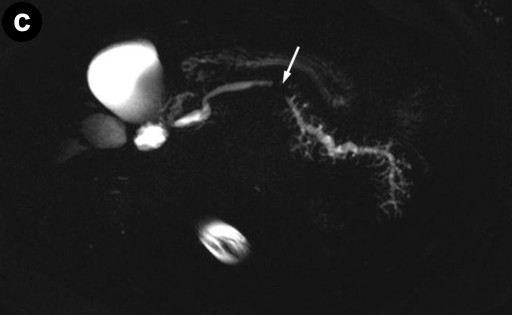

Contrast-enhanced MRI and diffusion-weighted imaging showed: a) an enlarged pancreas associated with highly restricted diffusion and delayed enhancement of the pancreas parenchyma as well as capsule-like peripheral enhancement in the late venous phase; b) main pancreatic duct strictures and chronic pancreatitis changes, suggesting possible autoimmune pancreatitis or a diffuse inflammatory process (Figure 1abc). Multiple mesenteric lymph nodes and two right renal mass-like lesions were also evidenced. 18F-fluorodeoxyglucose positron emission tomography/computed tomography (FDG-PET/CT) showed hypermetabolic activity within all lesions seen on MRI as well as less intense hyperactivity at the level of enlarged bilateral axillary lymph nodes (Figure 1d). These findings raised the hypothesis of lymphoma or tuberculosis. Endoscopic ultrasonography found a diffuse enlarged pancreatic gland and a 40 mm right renal mass. Fine needle aspiration (FNA) was performed both in the pancreas and in the kidney. Cytology showed non-specific inflammatory cells (Figure 2). IgG4-immunostaining was negative, serum IgG4 level was normal and anti-nuclear antibody was negative. Ultrasound-guided percutaneous renal biopsy was inconclusive, revealing a normal renal parenchyma. Cultures (containing a medium specific for mycobacteria and fungus) on FNA and percutaneous renal biopsy specimens were negative.

Figures 1. a. Fusion of axial MRI T2-weighted spin-echo and diffusion-weighted images showing high-intensity focal lesions in the pancreatic head (white arrow) and in the right kidney (black arrow). b. Late venous phase of contrast-enhanced axial MRI T1-weighted gradient-echo image showing a diffusely enhanced and enlarged pancreas with a high intensity capsule-like rim (arrows). c. MRCP image revealing a long segmental stricture (arrow) as well as dilatation and side branch ectasia of the main pancreatic duct. d. FDG-PET/CT showing multiple localizations of intense abnormal radiotracer uptake corresponding to the superior and inferior pole of the right kidney (open arrows), the head and body of the pancreas (closed arrows), and the axillary regions (arrowheads). |